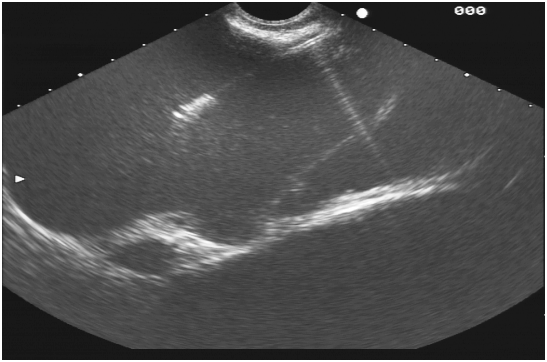

Blood studies for complete blood count; prostate specific antigen and hydatid serology were done and turned out negative. Due to the lack of a specific diagnosis, a rectal EUS was scheduled. Rectal EUS showed a large cystic anechoic lesion (Figure 2) located in the retro-rectal area with few septations and debris. After localizing the lesion, an FNA with a 22 gauge needle was done and a dark brownish fluid was aspirated (Figure 3). The fluid was sent for analysis and turned out to be hemorrhagic fluid in nature. At the end of the procedure, a total of 600ml of hemorrhagic fluid was aspirated resulting in almost total disappearance of the lesion and marked improvement in symptoms and relief of the low back pain.

Figure 2 EUS image showing the tip of the FNA needle inside the cystic mass.